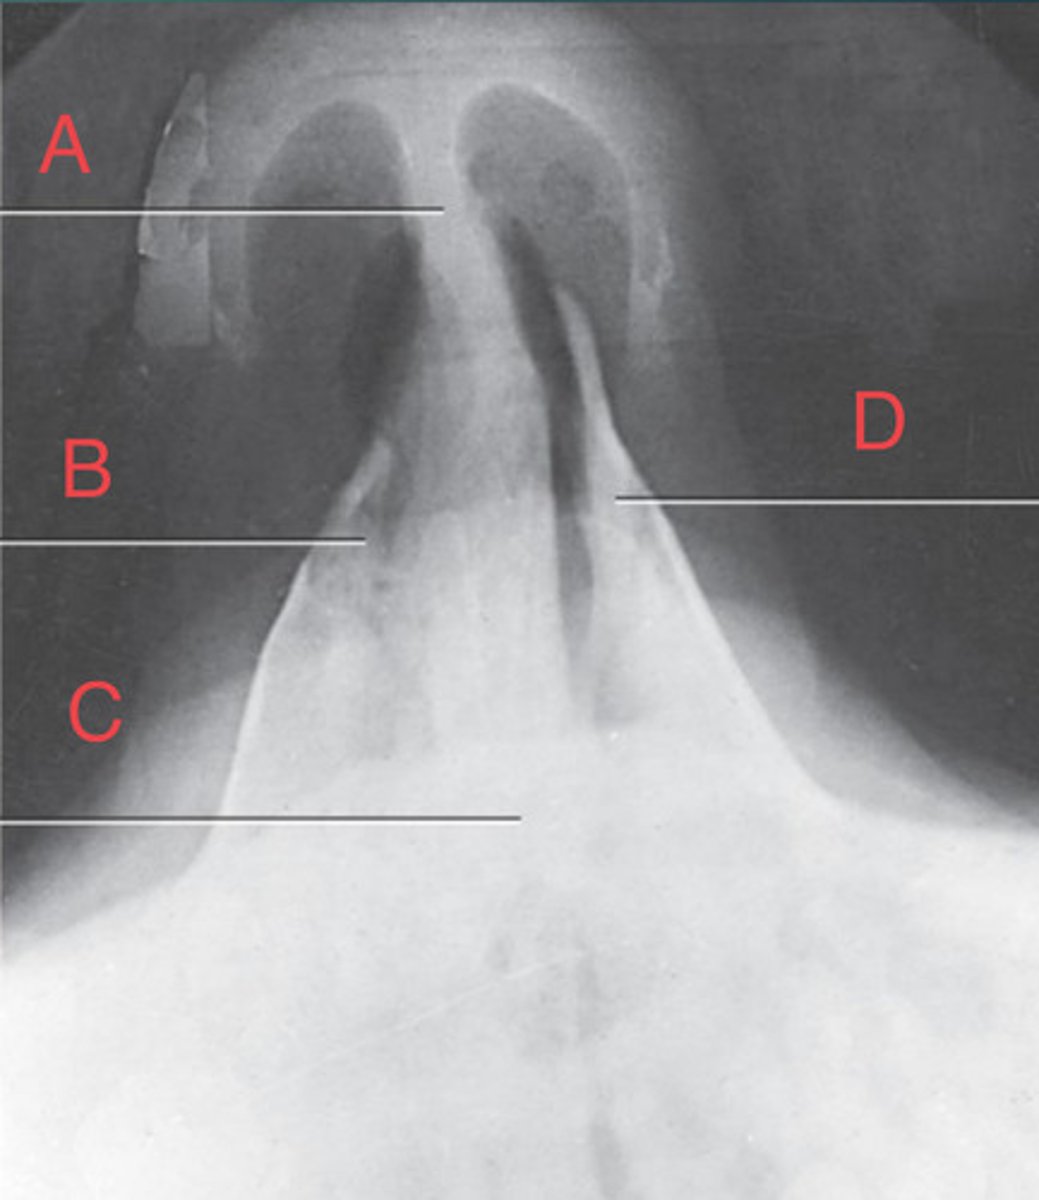

PA Caldwell Sinuses

frontal sinus of the frontal bone

A.

R. ethmoid sinus of the ethmoid bone

B.

crista galli of ethmoid bone

C.

L superior orbital fissure of the sphenoid

D.